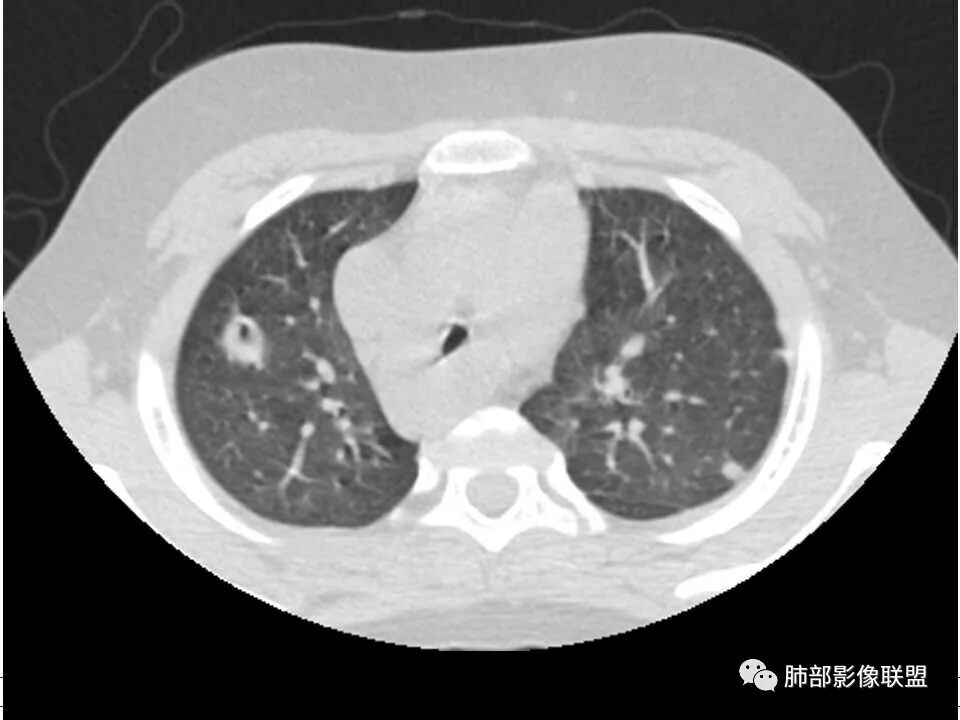

患者儿童,因右下肢疼痛伴肿胀14天就诊。病程中有发热及伴随症状。膝关节MRI提示右侧膝关节及右髌骨髁异常信号影,右膝髌上囊及关节腔内少量积液。胸部CT:双肺胸膜下多发结节影,部分结节空洞形成,且结节周围可见血管集束征。综合考虑血源性脓毒性肺栓塞、坏死性肺炎。右侧骨髓炎、血播性金葡菌肺炎,鉴别其他特殊感染及血管炎。

胸部ct:双肺多发空洞,结节,外带下叶为主,空洞内外光滑,有血管滋养征,综合病史及影像考虑脓毒性肺栓塞,结合病史,金葡可能性大。

2.双肺多发片影,随机分布,多空洞或囊腔,胸膜下多楔形影,气道未见受累等等符合脓毒血症影像学表现,尤其是金葡。

1. 多发胸膜下外周结节、< 3 cm 的楔形影和滋养血管征 CT 表现;

4.经恰当的抗生素治疗,肺部浸润影吸收。滋养血管征为一支血管影连接肺部周边病灶,在 2/3 以上患者出现,可作为高度提示 SPE 的征象。